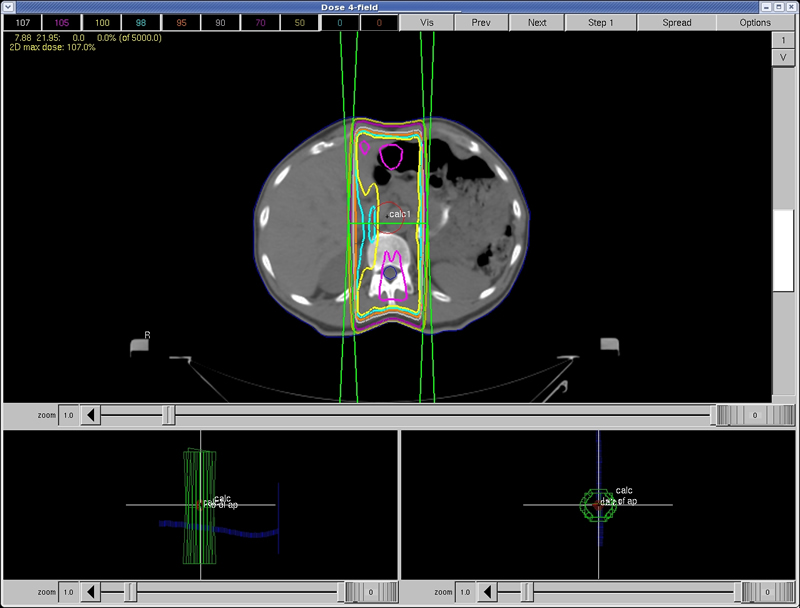

Lesson: 2 Fld vs. 4 Fld Module

If a physician prescribed a dose of 300 cGy x 10 (total 3000 cGy), this would be an acceptable treatment plan. However, if you are asked to take this to 5000 cGy, the spinal cord will receive too much dose.

Refer to the general Dose Tolerance table in the Reference Materials section.